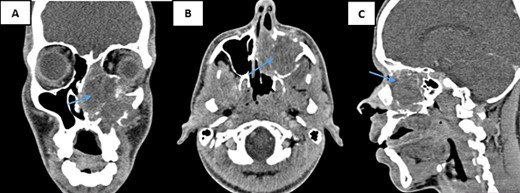

A nasal sinus computed tomography (CT) scan revealed a sizable tumoral mass measuring 60 × 47 × 46 mm, displaying heterogeneous tissue density enhancement following contrast injection. This mass originated from the nasal fossa and infiltrated several structures. Internally, the nasal septum and sphenoidal sinus; externally, the left maxillary sinus and the pterygopalatine fossa. Additionally, it involved the rectus inferior muscle, the floor, and the upper pole of the left orbit above, while causing localized lysis of the hard palate below. Posteriorly, the nasopharynx appeared intact (Fig. 1). Based on these findings, a malignant transformation of an inverted papilloma was suspected.

CT scans of the facial mass in coronal (A), axial (B), and sagittal (C) reconstructions were performed after the injection of iodinated contrast medium. The scans show a tumor (60 × 47 × 46 mm) on the left side (arrow) with hypodense tissue density. The tumor is heterogeneously enhanced after contrast injection and involves the nasal cavity and ipsilateral maxillary sinus, with aggressive infiltration of surrounding structures.